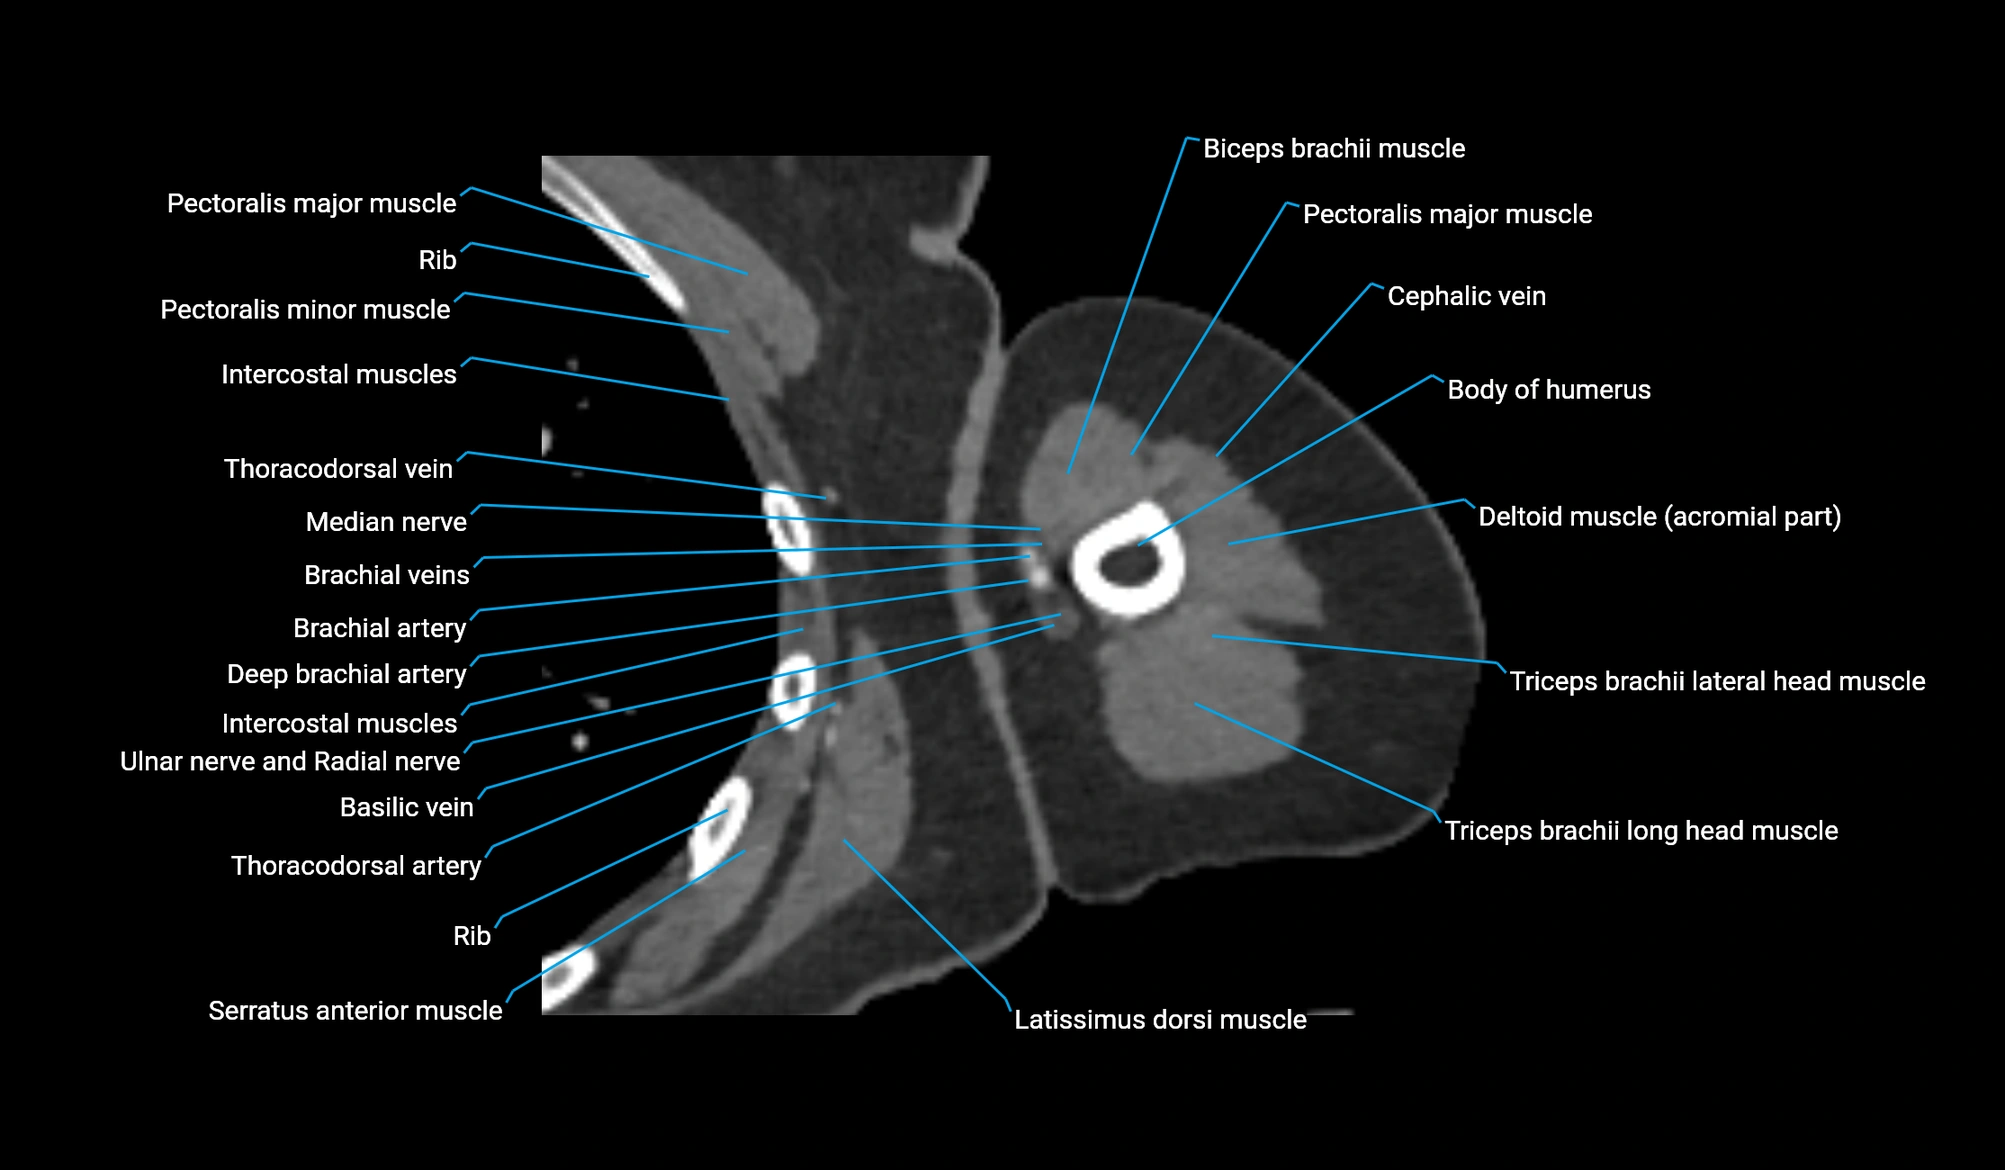

CT image